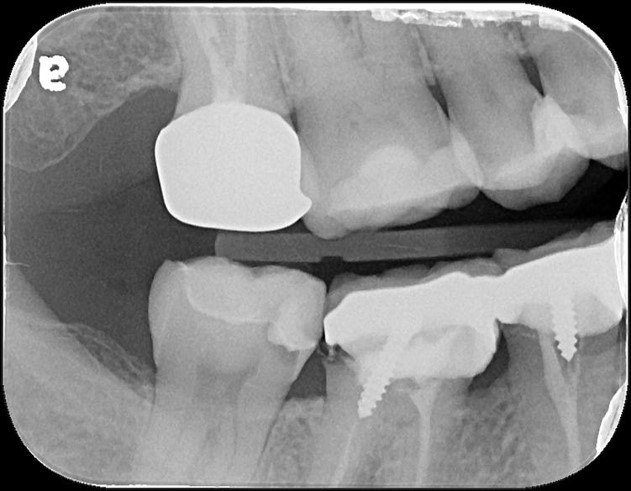

術前、術後比較